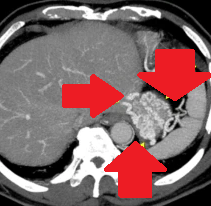

Polycystic liver disease. Red arrow. Infected hepatic cyst (Courtesy Dr. V. Penopoulos)